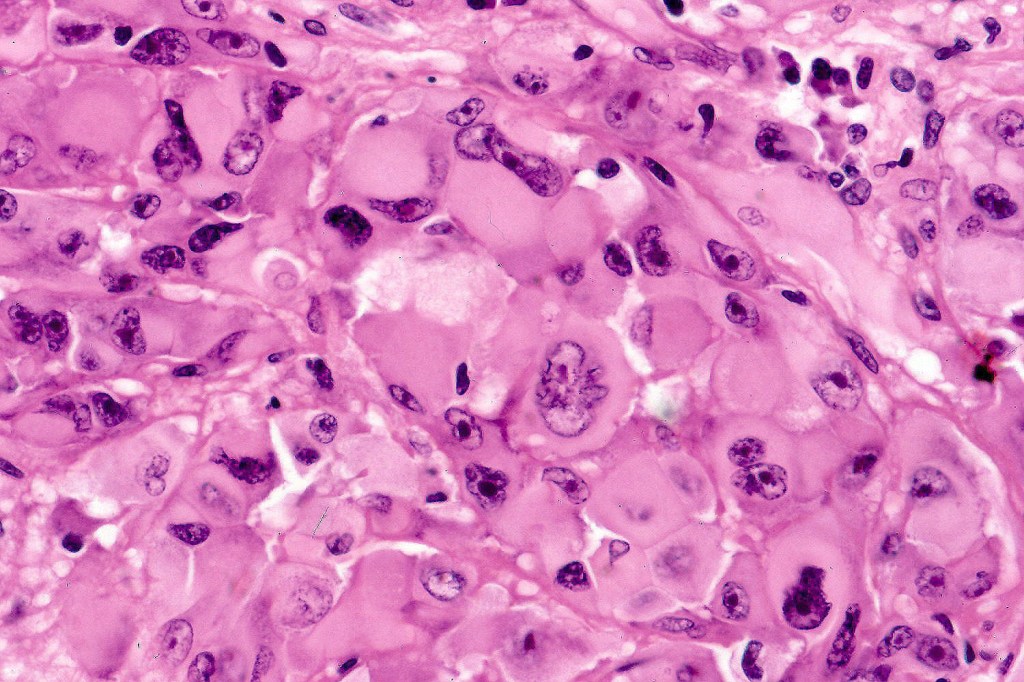

•Characterized by pleomorphic tumor cells with large eosinophilic, hyaline globular inclusions and eccentric vesicular nuclei containing prominent nucleoli, mitoses often conspicuous

•Inclusions predominantly composed of vimentin intermediate filaments

•Differential diagnosis includes rhabdoid change in renal cell carcinoma, malignant peripheral nerve sheath tumor, synovial sarcoma, extraskeletal myxoid chondrosarcoma, leiomyosarcoma proximal epithelioid sarcoma & rhabodid tumor in infants. There is a superficial resmblance to the inclusions seen in BAP1-inactivated melanocytoma but the frankly malignant nature of the rhabdoid cells, history of a primary tumor in the majority of cases and loss of BAP1 in BAP1-inactivated melanocytoma makes for ready distinction.

In this example, rhabdoid change accounted for only a small component of the tumor. IHC is S100